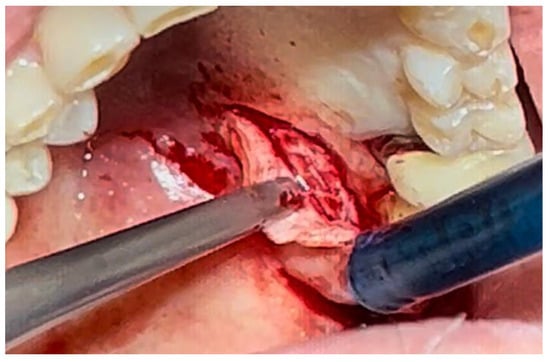

The patient was prepared for the surgical procedure with antibiotic therapy (Amoxicillin + Clavulanic Acid 875/125 mg) and 2% Chlorhexidine rinses starting the day before the surgery. Following the guidelines for patients with hypertension (Figure 1), the excision was performed with the complete removal of the lesion, adhering to standard surgical procedure techniques (Figure 3). Post-excision, hemostasis was achieved using Glubran II surgical glue. In this case, an endodontic needle was used for material application, allowing single droplets to be applied directly to the surgical site (Figure 4). Hemostasis was rapidly achieved in the areas where the glue was applied. The material was carefully deposited around the perimeter of the surgical site, ensuring individual droplets were placed without excessive application (Figure 5).

Figure 3. Surgical excision of the white lesion located on the palate with wide safety margins.

Figure 4. Hemostasis control at the surgical site following excision of the lesion with Glubran II using an endodontic needle.